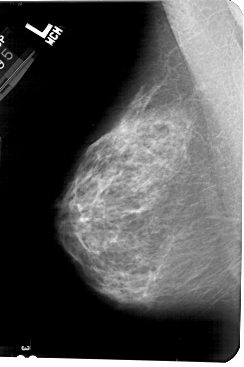

A_1569_1.LEFT_CC

LEFT_CC LINES 5491 PIXELS_PER_LINE 3391 BITS_PER_PIXEL 12 RESOLUTION 43.5 NON_OVERLAY